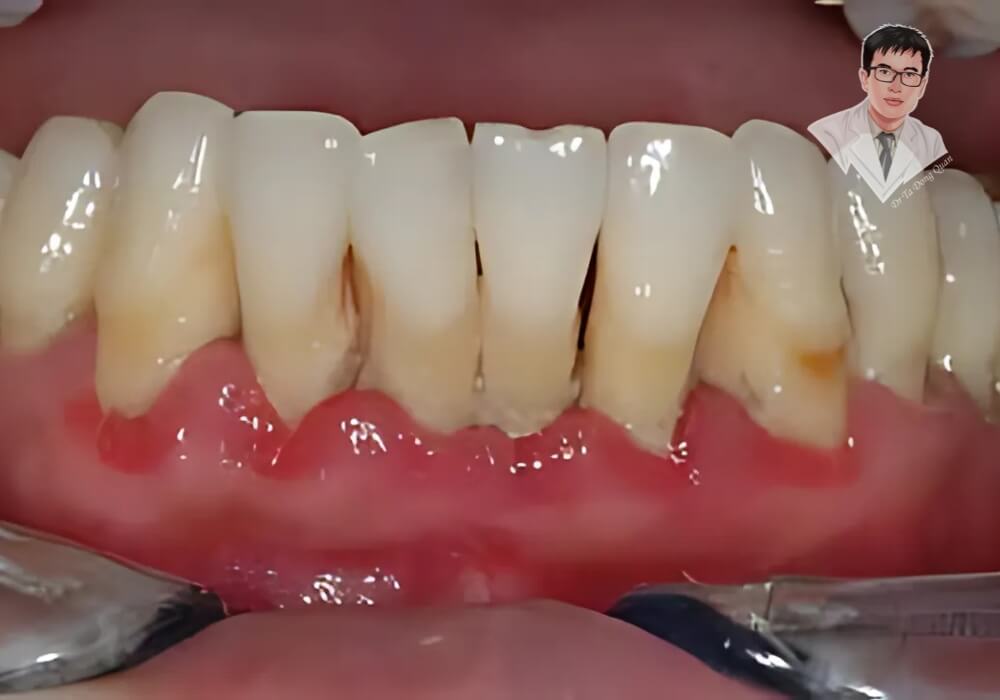

Bệnh tụt nướu răng xảy ra khi mô nướu co rút, làm lộ chân răng và khiến răng trở nên nhạy cảm. Đây là dấu hiệu cảnh báo sức khỏe răng miệng suy giảm, có thể dẫn đến viêm nha chu, sâu răng, thậm chí mất răng nếu không được điều trị kịp thời.

1. Chân Răng Lộ Rõ

Dấu hiệu dễ nhận biết nhất của bệnh tụt nướu răng là răng trông dài hơn bình thường do phần chân răng bị lộ. Khi mô nướu co rút, không còn che phủ hết chân răng, răng trở nên nhạy cảm hơn và dễ bị tổn thương.

4. Nướu Sưng Đỏ, Đau Nhức

Tụt nướu răng không chỉ làm lộ chân răng mà còn khiến nướu dễ bị viêm nhiễm. Khi vi khuẩn tấn công, nướu có thể sưng đỏ, đau nhức và trở nên nhạy cảm hơn.

- Nướu có màu đỏ thẫm thay vì hồng nhạt.

- Xuất hiện cảm giác đau hoặc nhức nhẹ ở vùng nướu bị tụt.